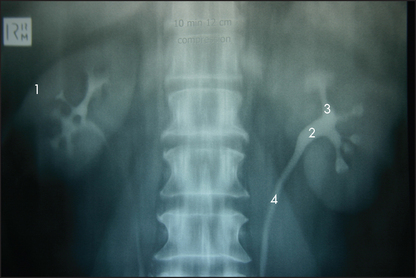

The presence of a Tenckhoff catheter (peritoneal dialysis catheter) should be noted. It is important to look for nephrectomy scars (see Figure 14.24, page 195). These are often more posterior than one might expect. It may be necessary to roll the patient over and look in the region of the loins. Renal transplant scars are usually found in the right or left iliac fossae. A transplanted kidney may be visible as a bulge under the scar, as it is placed in a relatively superficial plane. Peritoneal dialysis results in small scars from catheter placement in the peritoneal cavity; these are situated on the lower abdomen, at or near the midline.